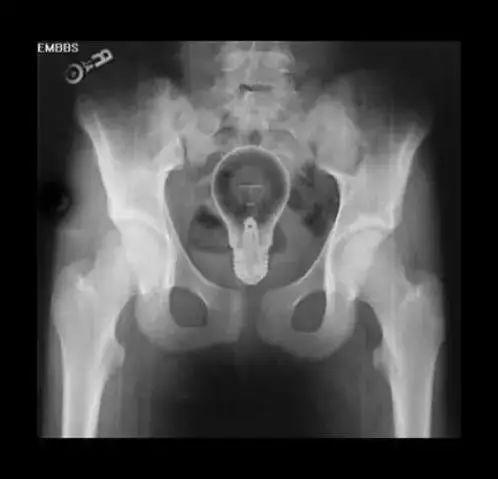

首先,医生会用指诊 、X线等等一系列的办法,来确定里面的异物是什么、在什么位置。这一点很关键,因为患者的描述可能很不清晰,甚至还会撒谎。而搞清楚里面真正的情况,这样才能找到合适的方法把它取出来。

一个灯泡。

我知道大家的心情是复杂的,但“菊科”大夫见多识广,会严肃对待哪怕再猎奇的病例。请不要因为害羞尴尬就拖延就医或欺骗大夫!